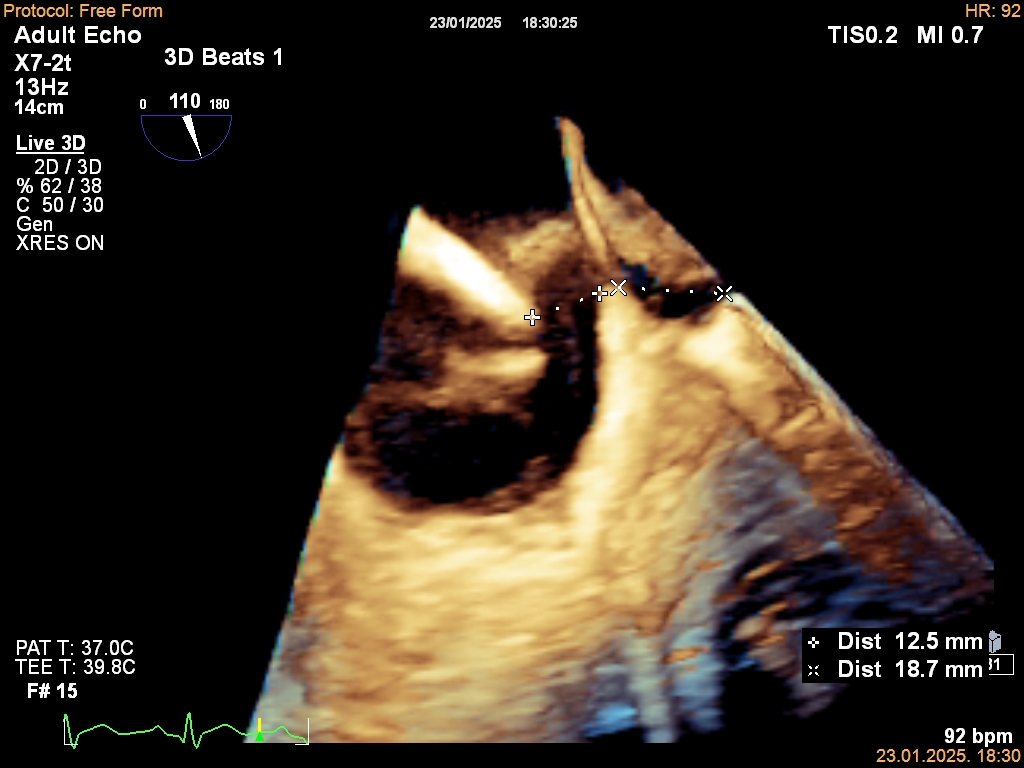

- Prednosti 3D transezofagealne ehokardiografije u dijagnozi i prognozi infektivne endokarditisa

(⬇️ Preuzmite PDF) - AI EKG za predikciju srčane slabosti s reduciranim EF: pregled i meta-analiza